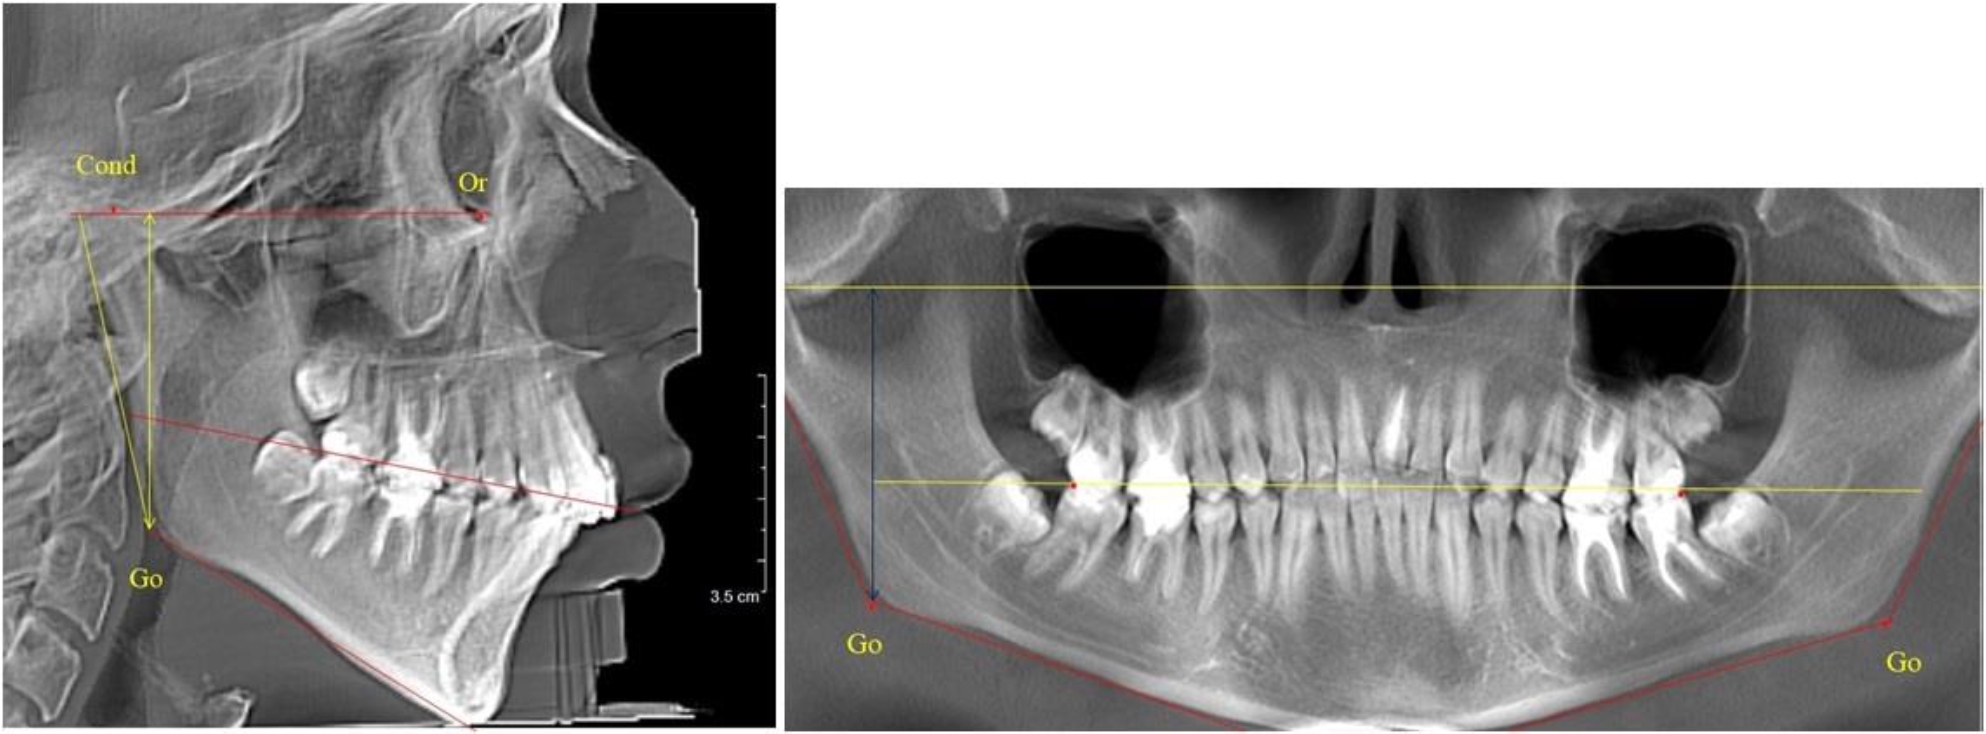

На всех парах рентгенограмм угол нижней челюсти, измеренный на телерентгенограмме, так же, как и в 1-й группе, соответствовал углу, полученному при построении угла на ортопантомограмме. Окклюзионная линия делила ветвь на два отдела (рис. 2).

Рис. 2. ТРГ и ОПТГ пациента после прорезывания первых постоянных моляров

Как на ортопантомограмме, так и на телерентгенограмме высота ветви у детей 2-й группы составляла (46,54 ± 2,87) мм, что было несколько больше, чем у детей 1-й группы (р ˂ 0,05). При этом высота верхней окклюзионно-суставной части была (25,42 ± 1,59) мм, а нижней – (21,12 ± 1,77) мм.

Таким образом, верхняя часть была несколько больше нижней, что и определяло рост обеих частей ветви.

Относительные показатели соразмерности частей ветви нижней челюсти показали, что отношение высоты верхней части ветви к нижней в среднем составляло 1,21 ± 0,12. Отношение общей высоты ветви к верхней ее части составляло 1,83 ± 0,13, а отношение общей высоты ветви к нижней ее части было 2,20 ± 0,16, и достоверных различий по относительному показателю отношения всей высоты к верхней и нижней челюсти нами не отмечено (р ˃ 0,05).